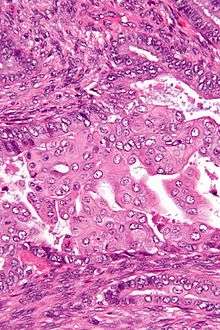

Micrograph of an atypical polypoid adenomyoma. H&E stain. | |

APAs are characterized by glands with abnormal shapes that: (1) often have squamous metaplasia, and (2) are surrounded by benign smooth muscle.[1] Nuclear atypia, if present, is mild.

The microscopic differential diagnosis includes endometrial carcinoma and endocervical adenocarcinoma.